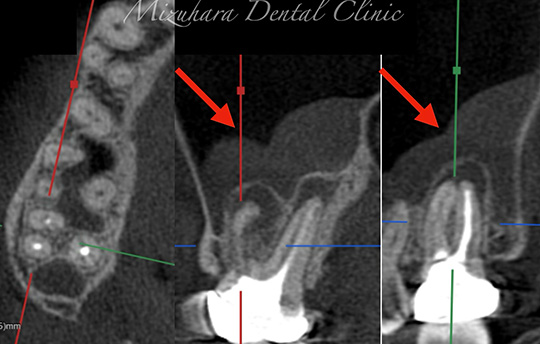

保存可能な歯を見極め

予知性の高い治療を提供できるだけ患者様の大切な歯を残し、10年、20年先まで健康な状態を保てるよう、長期的な視点で治療を計画します。そのために最も重要なのが、「診査」と「診断」です。的確な診断は精密な診査から生まれ、治療結果を大きく左右します。問診や簡易検査だけでは見逃されがちな病変も、CTやマイクロスコープなどの最新の医療機器を活用し、時間をかけて丁寧に「診査・診断」を行います。